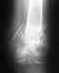

Без снимка не ответить. Вообще, правильно введенный внутрикостный стержень не мешает движениям.